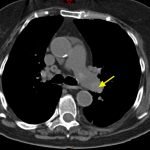

Non-contrast CT of the chest demonstrates hyper-densities within both central and sub-segmental pulmonary arteries bilaterally (see yellow arrows). The right ventricle is dilated.

The diagnosis of pulmonary embolism is usually made by visualizing intravenous contrast filling defects within the pulmonary arteries on CT angiography of the chest. Ventilation perfusion scanning is an alternative modality, but was not available in this case. A hyper-dense lumen sign on non-contrast chest CT1 can identify pulmonary emboli with a reported sensitivity of 36%.2

Utilizing non-contrasted CT of the chest to identify hemodynamically significant central thrombi when IV contrast is not an option may allow for initiation of therapy in a timely manner or may help identify PE when it may not be the primary consideration.